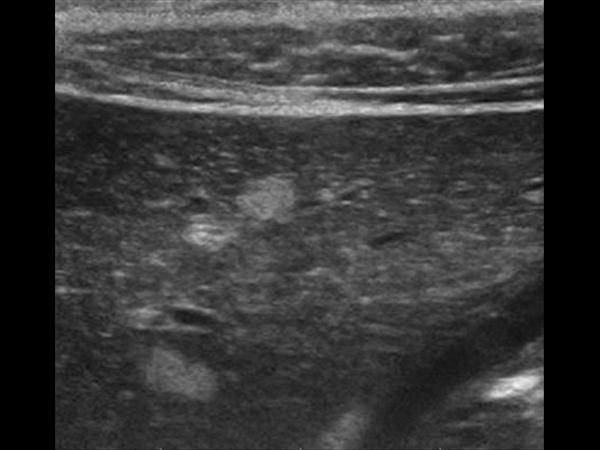

Gan nhiễm mỡ

Gan nhiễm mỡ - Ảnh 4

» Thông tin: Nữ giới – 56 tuổi.

» Lâm sàng: Kiểm tra sức khỏe.